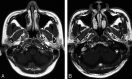

Fig 4.

Axial T1-weighted contrast-enhanced MR image of the nasopharynx in a patient with suspected NPC (group 2) where MR imaging incorrectly diagnosed cancer that was later shown by biopsy to be lymphoid hyperplasia. A, Section at the level of the fossa of Rosenmuller shows mucosal abnormality in the fossa bilaterally (arrows), giving the false-positive result on MR imaging for cancer. B, Section at the level of the roof shows the “striped” appearance of normal lymphoid tissue in the adenoids (arrows).